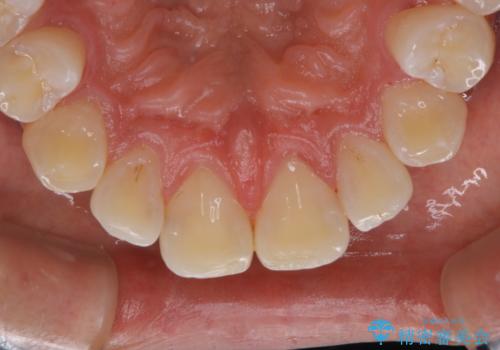

PMTC60分コースを行いました。

- ¥11000費用は治療当時の料金となります